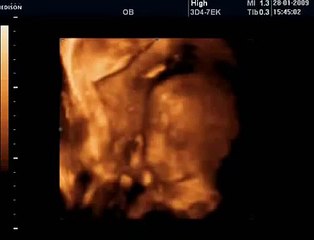

www.cemturan.combr www.dr-cemturan.combr www.jinekolojikonkoloji-istanbul.combr www.perinatoloji-istanbul.combr Hamilelikte renkli Doppler ultrason niçin yapılır? Bebek renkli mi görülür yoksa damarları görmek için mi renkli Doppler yapılır? Prof. Dr. Cem Turan'dan izleyin. Renklli doppler ultrason ile en çok incelenen damar bebeğin göbek kordonundaki damarlardır (umblikal damarlar). Bunun dışında rahim damarları, beyin damarları, kalp damarları gibi çeşitli damarlar incelenebilir. Özellikle rahim içerisinde gelişme geriliği (iugr) şüphesi olan bebeklerde, anomali varlığında, kalp ritm bozukluğu veya kardiyak anomali varlığında, yüksek tansiyon hastalarında yapılır. Her gebelikte rutin olarak yapılan bir inceleme değildir.